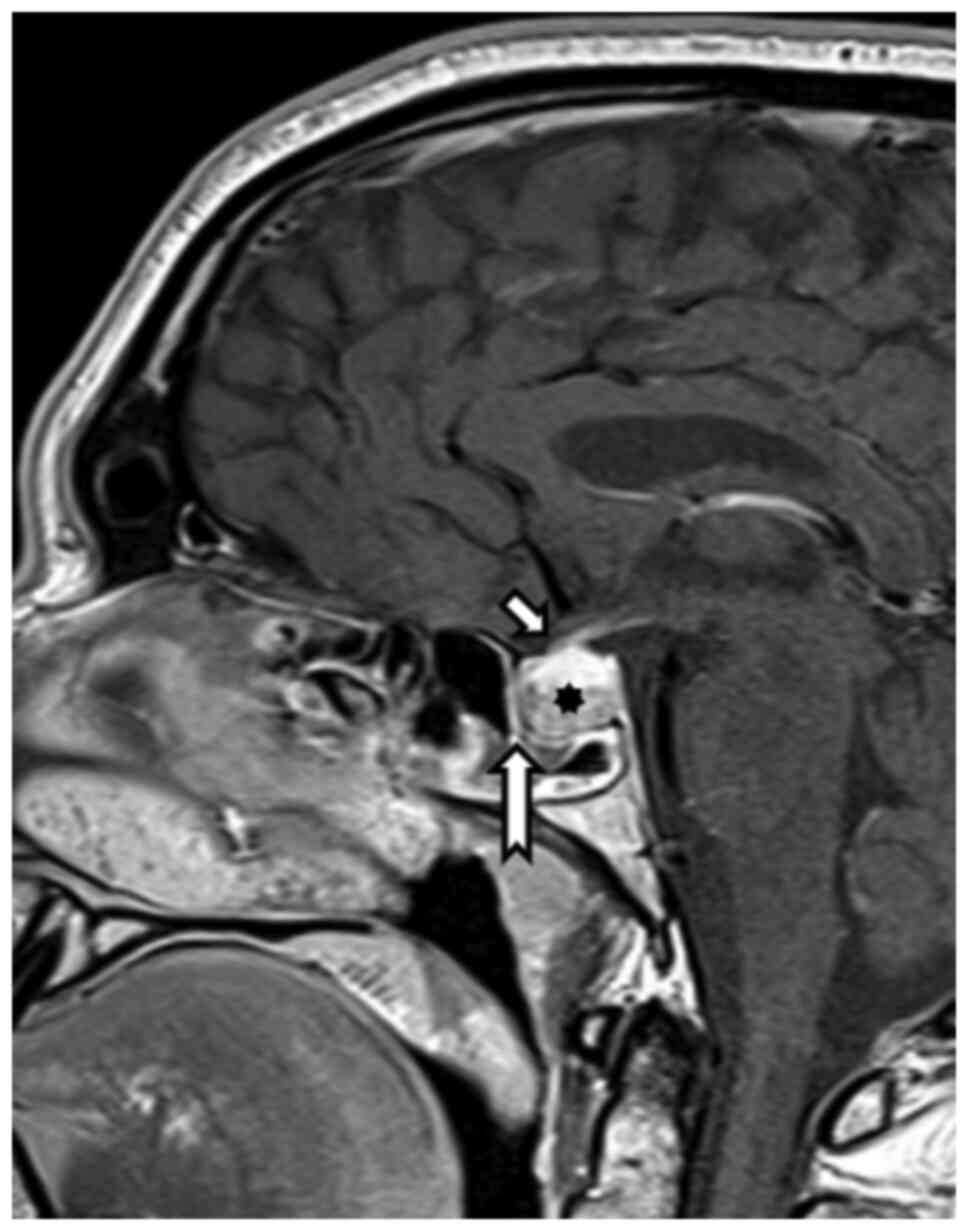

Structural MRI of the hypophysis and orbits was carried out on a 3T Achieva dStream TX SERIES (Philips HealthCare, Best) with a 32-channel SENSE RF head coil. The hypophysis was examined according to the protocol, with intravenous application of 10 ml of gadolinium contrast substance. MRI of the hypophysis employed a T1 TSE sagittal sequence, with 2-mm slice thickness, gap 0, TR 500, TE 10 native and after intravenous contrast substance application (Fig. 5). The targeted orbital examination employed an sT1 3D TFE sequence, with 1-mm-slice thickness, gap 0, TR 6.7, TE 3.1, primarily in the sagittal plane, T2 TSE mDIXON, 2.5-mm-slice thickness, gap 0.3, TR 3000, TE 80, in the coronal plane and targeted orbital sequences on both sides, T2 SPIR SSh, 3-mm-slice thickness, gap 0.3, TR 9520.2, TE 120.0. Optic nerve measurements were analyzed on IntelliSpace Portal working station version 10-1 (Philips Medical Systems). Coronal T2 SPIR SSh sequences were planned in the axial plane upright to the optical nerve in 4-8-16-20-mm intervals behind the dorsal eye contour for both sides. The measurement included the optic nerve's largest outer diameters in two perpendicular axes horizontally (ONDH) and vertically (ONDV), and optic nerve sheath diameters in two perpendicular axes horizontally (OSDH) and vertically (OSDV) in both previously mentioned intervals separately (Fig. 6 and Table I). The optic nerve chiasma was detected in the coronal plane in the T1 TFE 3D sequence at the point of its narrowest range, and the outer diameter in the horizontal plane was measured. The Parks et al algorithm was used to distinguish PA from craniopharyngioma (13).

Figure 5

Control magnetic resonance imaging after one year. T1 postcontrast sequence, sagittal plane. The non-homogeneous hypophyseal structure persists. The growth of cranial hypophyseal contours from the optic nerve chiasm was evident. Short arrow indicates chiasm, long arrow indicates tuberculum sellae and asterisk indicates hypophysis.

Figure 6

(A) Magnetic resonance imaging sequence for the dimensional assessment of the optic nerve and its sheath (red planning line). (B) T1 Turbo Field Echo planning axial sequence for the coronal plane projecting vertically to the optic nerve and the right eye. (C) Coronal T2 Spectral Presaturation with Inversion Recovery Single Shot sequence for measurement of the right eye. HOSD, horizontal optic nerve sheath diameter; HOND, horizontal optic nerve diameter; VOSD, vertical optic nerve sheath diameter; VOND, vertical optic nerve diameter.